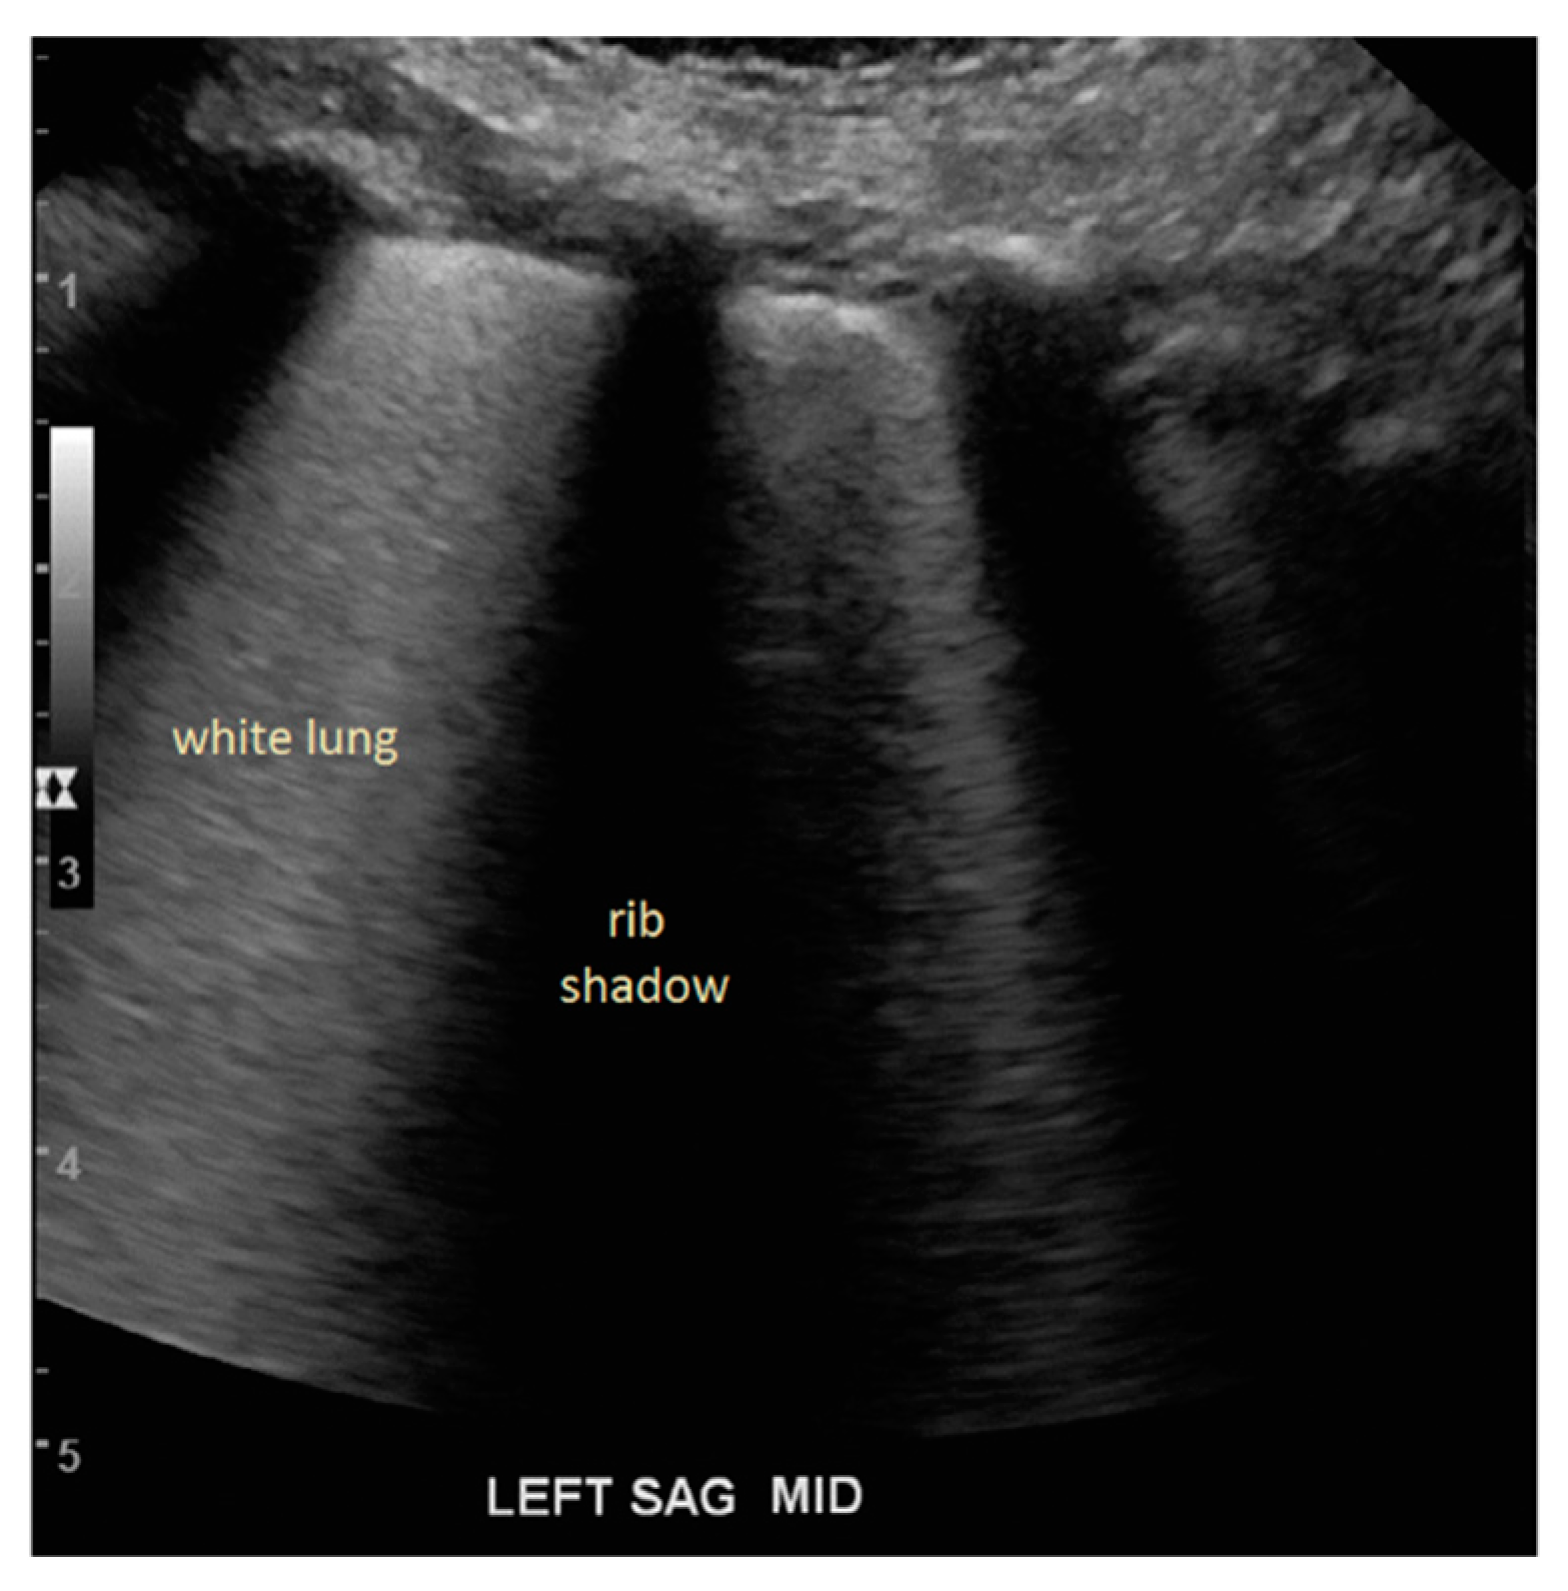

Later work investigated PFC filling in vivo by Lesser et al. [18] using porcine models and Degnan et al. [19] in infants. In these undertakings, visualization of central structures was not found and sonography appear as white lung syndrome with low penetrability in absence of A Lines (Figure 2). Table 2 summarizes the literature with corresponding sonographic finding of a PFC filled lung.

Figure 2. Sonographic image of the lung during static PFC administration in infants showing white lung between the rib shadows without the visualization of lung structure and absence of A-lines. (With permission from Degnan et al. [19]).